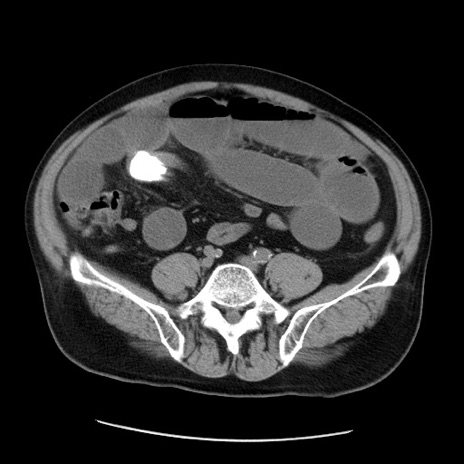

症例20(横断像)

【症例】 60歳代男性

【主訴】 腹部膨満、嘔吐

【現病歴】5日前頃より倦怠感を認め食事量減少し4日前の朝嘔吐、食事摂取困難となった。 3日前近医受診し点滴施行され整腸剤などを処方された。 当日他院を受診し、腹部膨満著明、炎症反応の上昇(CRP10.8、WBC11200)あり、紹介受診となる。

【身体所見】 意識JCS1 受け答えがはっきりしないBP 111/57mHg、 P 67bpm、、BT35.2°C、SpO2 97%(RA)、 腹部:膨隆、打診で鼓音あり、全体的に圧痛有り、腸蠕動音(-)、反跳痛ははっきりせず。

【データ】WBC 11400、CRP 14.20